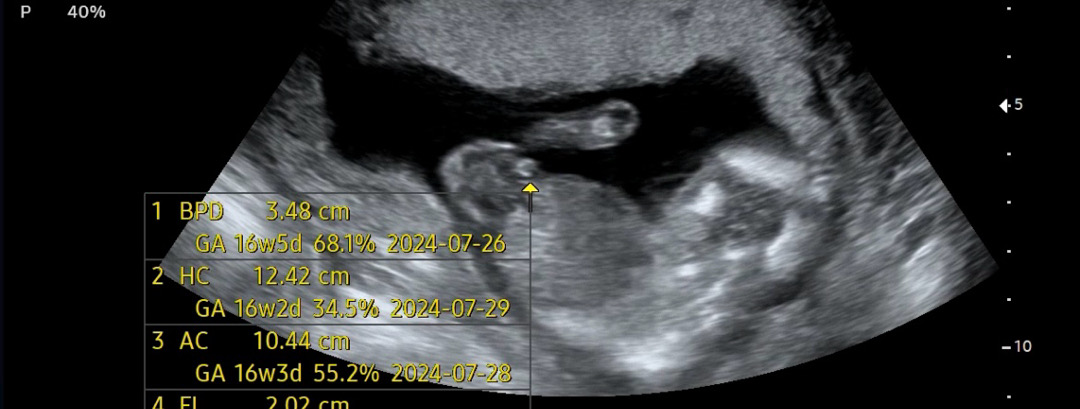

16주 아들인가요?

애기가 다리사이를 잘 안보여줘요 이거보구 뭐가 보이는거 같긴하네~ 하면서 화살표 해주셨는데...탯줄일수도 있나요?

너무 어렵네요ㅠㅠ 저는 고추 아들인거같아요